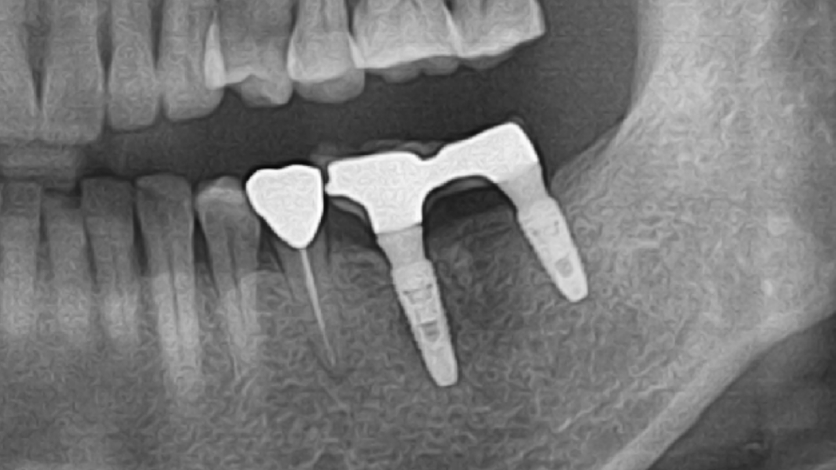

Clinical Cases

Video